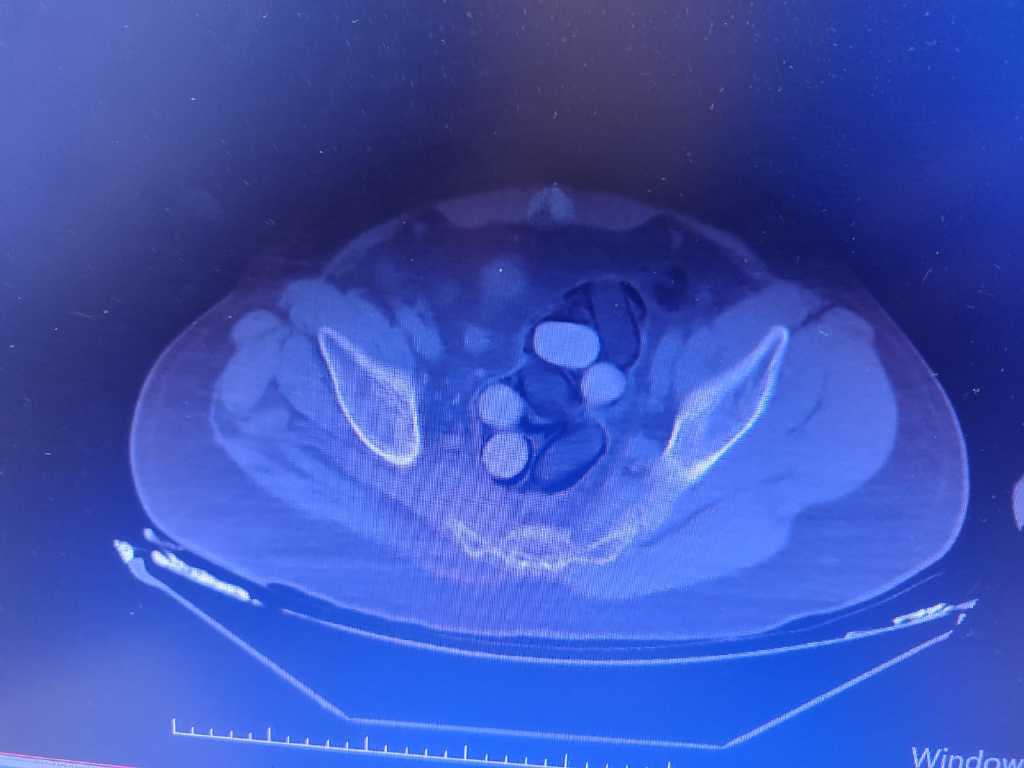

Gözaltına alınan yabancı uyruklu 2 kişiye, hastanede yapılan incelemeler sonucunda midelerinde 126 kapsül halinde 1 kilo 300 gram eroin ve 44 kapsül halinde 550 gram afyon sakızı olduğu görüldü.

Uyuşturucular, hastanedeki müdahalenin ardından şüphelilerin midesinden çıkarıldı. Y.S. ve H.S., emniyetteki işlemlerinin ardından çıkarıldıkları mahkemece tutuklanarak cezaevine gönderildi.